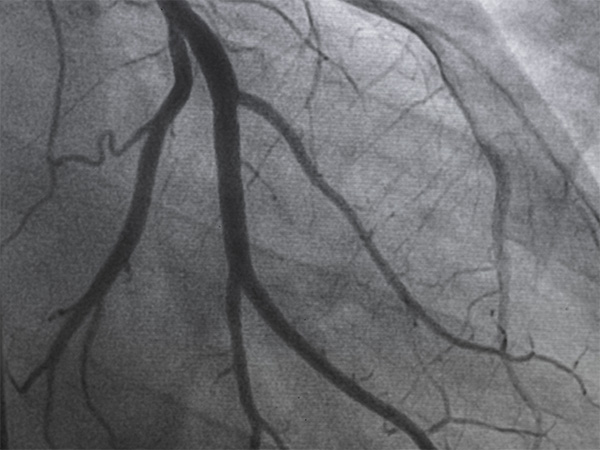

Mintz is pleased to have represented Royal Philips, a global leader in health technology, in entering into an agreement to acquire SpectraWAVE, Inc., an innovator in Enhanced Vascular Imaging of coronary arteries, angiography-based physiology assessments, and the use of AI in medical imaging. SpectraWAVE’s intravascular imaging and physiological assessment technologies provide advanced solutions for the treatment of patients with coronary artery disease, affecting more than 300 million people worldwide. The acquisition will expand Philips’ existing intravascular imaging and physiological assessment device portfolio to create a comprehensive offering in intravascular imaging and physiology solutions.